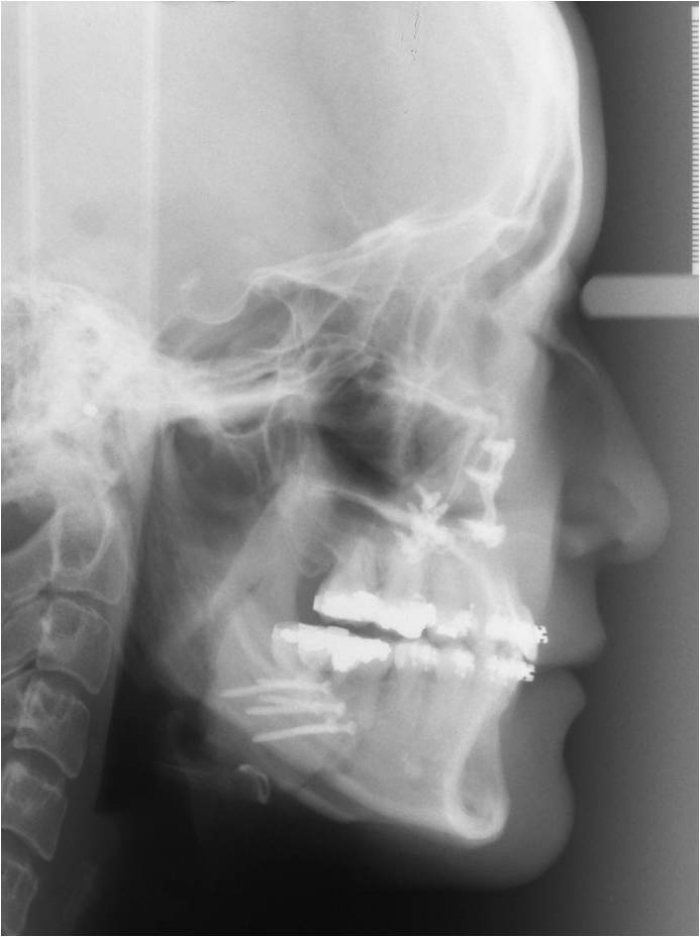

Telerradiografia inicial